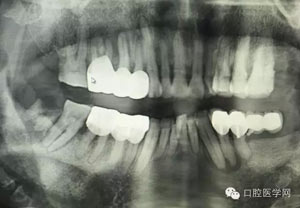

病例2:364647中齲的樹脂充填,現(xiàn)在樹脂的充填材料非常之多,有些時候,我們感覺有了好的材料我們就可以做出好的修復(fù),可是這是在我們有扎實的基本功的基礎(chǔ)上的,我們可以沒有那么好的樹脂,那么多的顏色選擇,修復(fù)的那么的逼真,但是我們至少要恢復(fù)患者牙齒的功能,將腐質(zhì)去除干凈,薄壁弱尖消除掉,選擇好適應(yīng)癥,給患者以盡可能好的修復(fù)。